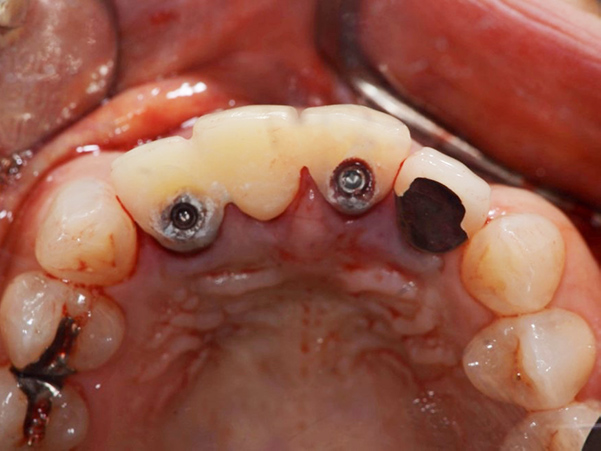

1次手術時の流れ

①手術開始時

②被せ物を外した状態

③抜歯

④サージガイドを使用したインプラント体の埋入

⑤インプラント体を埋入した状態

⑥仮歯を製作していく段階

⑦仮歯を装着した状態

埋入したばかりのインプラント体に負担がかからないように、下の歯と当たらないような形と噛み合わせになるよう調整しています。

手術後2weeks

歯ぐきの腫れもなく、経過は良好でした。

手術後1.5ヶ月

手術直後と比較すると、歯ぐきが少し下がってきていますが、それ以外に変化はありませんでした。